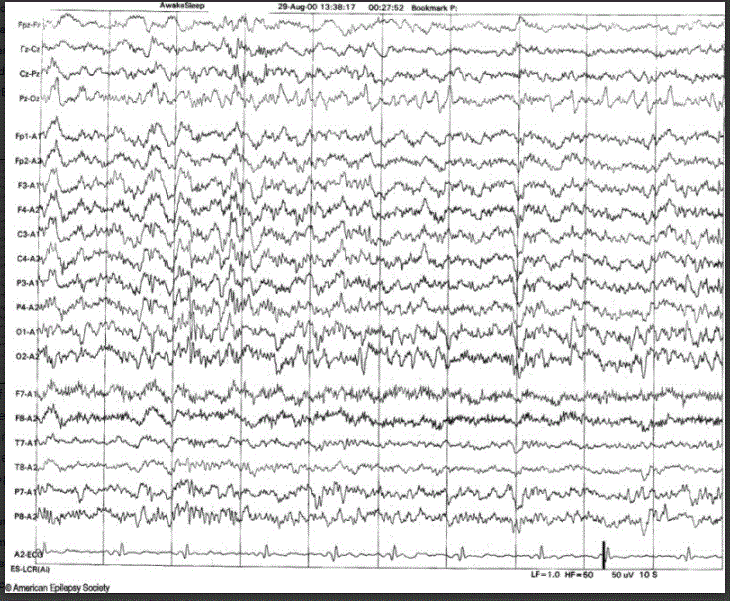

SREDA (Subclinical Rhythmic Electrographic Discharges in Adults))

• 5-6 Hz sharply contoured theta

• Diffuse but maximal over parietal and posterior temporal regions

• Seconds - 2 min (usually > 30 seconds)

• Drowsiness

• Usually abrupt onset and termination

• Hyperventilation can trigger

• Older adults (usually > 50 y/o)